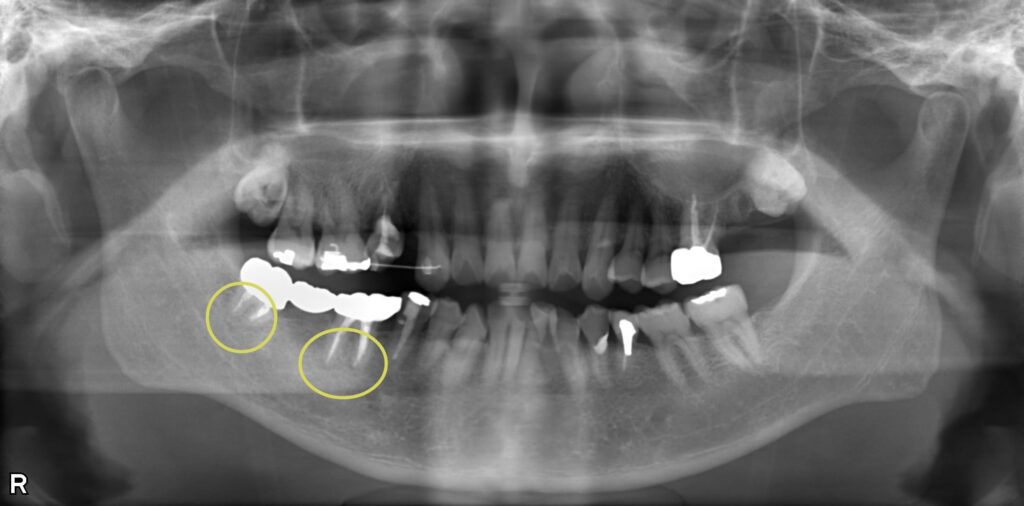

根管感染と虫歯を併発した複合症例の治療

右下がジンジンする、噛んでも磨いても痛いとのことで来院されました。 右下6番は根管内に感染を起こして透過像があり、右下8番は被せ物の中で虫歯になっていて、神経の炎症を引き起こしていました。 まず8番の抜髄処置を行い、緊密に根管充填したのち、6番の治療にも取り掛かりました。 どちらの歯も複雑な根管形態をしていたため、マイクロスコープを使用して丁寧に根管内を清掃しました。 術後の経過は良好で、透過像も消失しています。

| 概要 | 右下がジンジンする、噛んでも磨いても痛いとのことで来院されました。 右下6番は根管内に感染を起こして透過像があり、右下8番は被せ物の中で虫歯になっていて、神経の炎症を引き起こしていました。 まず8番の抜髄処置を行い、緊密に根管充填したのち、6番の治療にも取り掛かりました。 どちらの歯も複雑な根管形態をしていたため、マイクロスコープを使用して丁寧に根管内を清掃しました。 術後の経過は良好で、透過像も消失しています。 |

| 治療部位 | 右下6番、8番 |

| 治療内容 | 根管治療 |